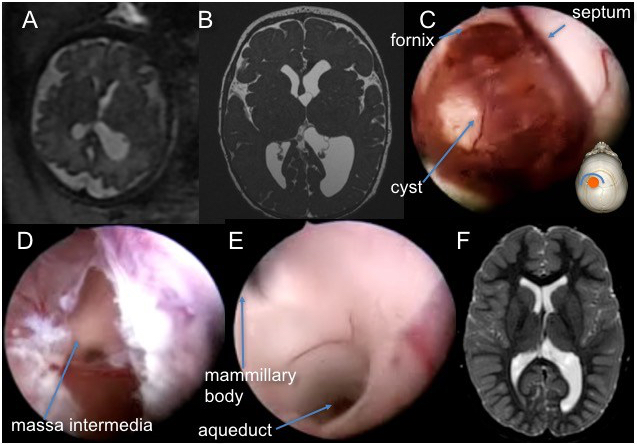

kyste suprasellaire

il s’agit d’un des grand succès de la fenestration endoscopique, qui en est le traitement de référence.

il est cependant indispensable :

- que les ventricules soient dilatés

- d’autre part il faut obtenir une communication entre le ventricule latéral, le kyste et les citernes, c’est à dire une ventriculo-kysto-cisternostomie.

dans les rares cas sans hydrocéphalie (chez le nourrisson en particulier), un abord direct par voie ptérionale peut être nécessaire.

visionner l’endoscopie pour kyste arachnoïdien supra-sellaire